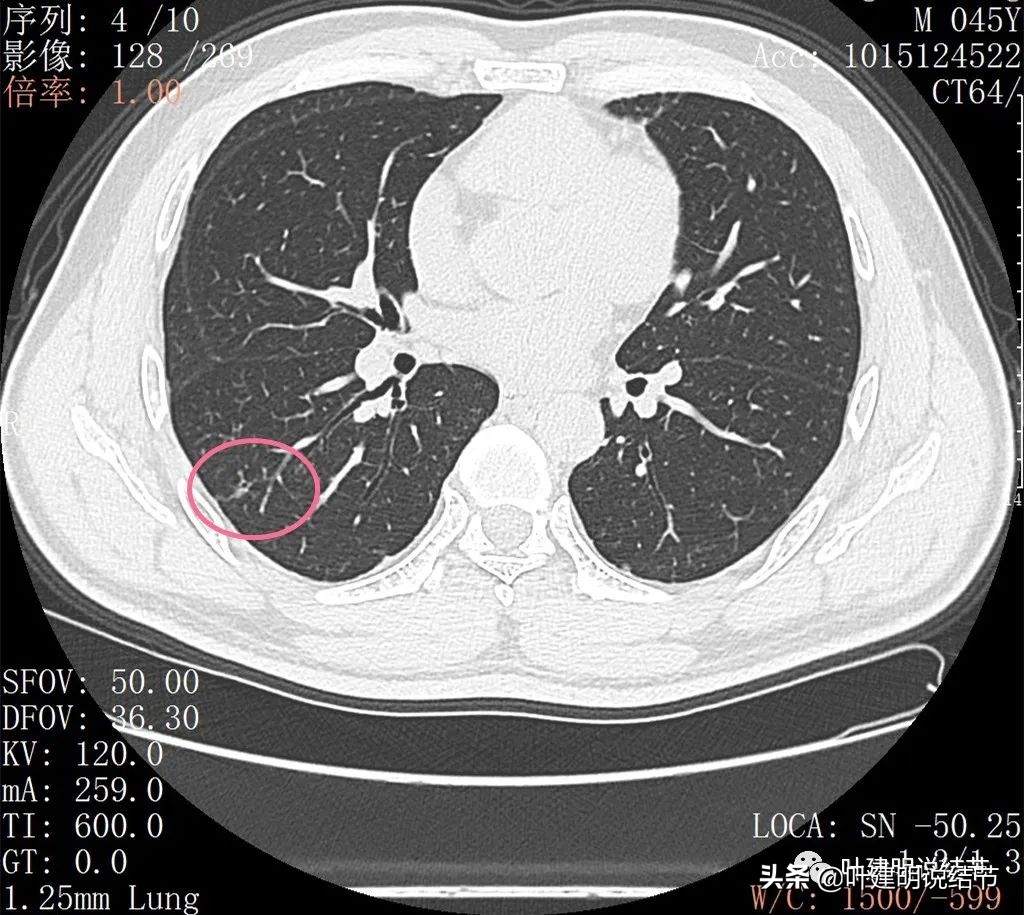

再来看薄层扫描:

边缘血管异常增粗(桔色箭头),边缘显糊(绿色箭头),细支气管扩张(黄色箭头)